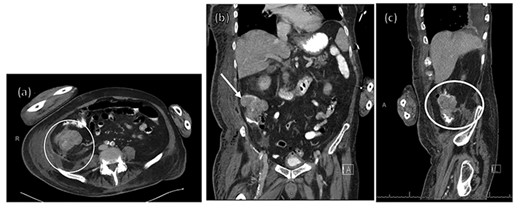

An 84-year old man presented to the Emergency Department from his nursing home acutely febrile and encephalopathic with melanotic stool. His pertinent past medical history included stroke with residual left hemiparesis and gastrointestinal bleed one year prior. He was not anticoagulated and had no surgical history or prior colonoscopy (Table 1). On initial evaluation his heart rate was 92, blood pressure 95/51, and he was obtunded. His laboratory values (Table 2) demonstrated acute anemia, acute renal failure, and concern for infectious process with procalcitonin of 14 ng/mL. His stool was grossly heme-positive. Physical examination revealed dry mucous membranes, a non-tender and non-distended abdomen, and no evidence of skin changes nor infection. He was volume resuscitated, initiated on broad spectrum antibiotics, and admitted to the intensive care unit (ICU) with presumed diagnoses of gastrointestinal bleed and sepsis of unknown etiology given an elevated lactic acid and procalcitonin with hypotension. Gastroenterology was consulted at the time of admission for endoscopy given his history of melanotic stool and anemia. Endoscopy was deferred after improvement with resuscitation and no continued evidence of active bleeding. After initial resuscitation his laboratory values and hemodynamics normalized and he returned to baseline mental status. He did not elicit history of weight loss, decreased appetite, recurrent melanotic stool, or alterations in bowel habits in the past year. Within 24 hours of ICU admission he developed right hip erythema, induration, and pain. On examination, there was no crepitus. CT of the right hip (Fig. 1) demonstrated concern for necrotizing soft tissue infection with gas involving the right retroperitoneum and upper thigh without evidence of abscess. General surgery was consulted for necrotizing fasciitis but due to the patient’s poor functional status and need for highly morbid surgery, operative intervention was declined by the patient’s durable power of attorney. He unexpectedly clinically improved with non-operative treatment over the following 32 hours, prompting evaluation for alternative etiologies of his soft tissue infection. CT of his abdomen and pelvis (Fig. 2) demonstrated a 7.1 cm proximal right colon mass with invasion into the retroperitoneum and gas tracking into adjacent soft tissues concerning for a perforated malignancy. A CT abdomen and pelvis were not obtained prior to this due to lack of abdominal symptoms, non-tender examination, and family decision for non-operative management. Colorectal surgery was consulted and although tumor resection with debridement would obtain source control, the widespread soft tissue infection would still require extensive debridement. After goals of care discussions, the patient and his family elected for palliative care. He was subsequently transitioned to hospice care and expired 10 days later.